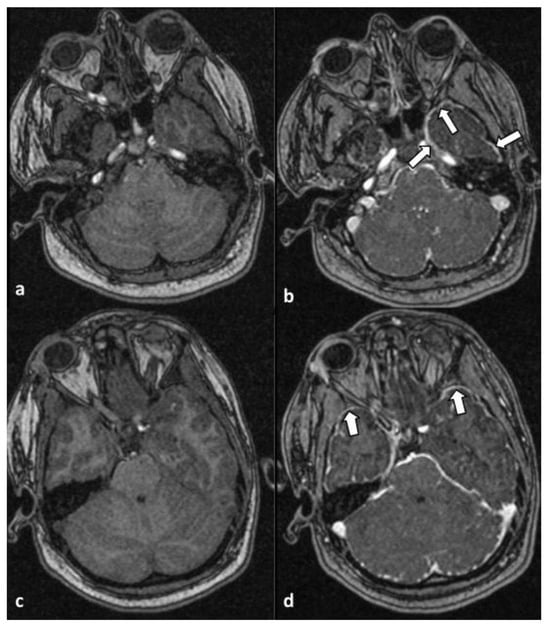

Moreover, infratentorial leptomeningeal enhancement, most prevalent along the anterior aspect of the temporal lobes (arrows), was observed in axial T1-weighted MR images without (a and c) and after (b and d) administration of intravenous contrast. The findings were suggestive of the presence of meningitis/meningoencephalitis (Figure 2).

Figure 2. Axial T1-weighted MR images without (a,c) and after (b,d) administration of intravenous contrast material. An infratentorial leptomeningeal enhancement was noted, most prevalent along the anterior aspect of the temporal lobes (arrows). The findings were suggestive of the presence of meningitis/meningoencephalitis.